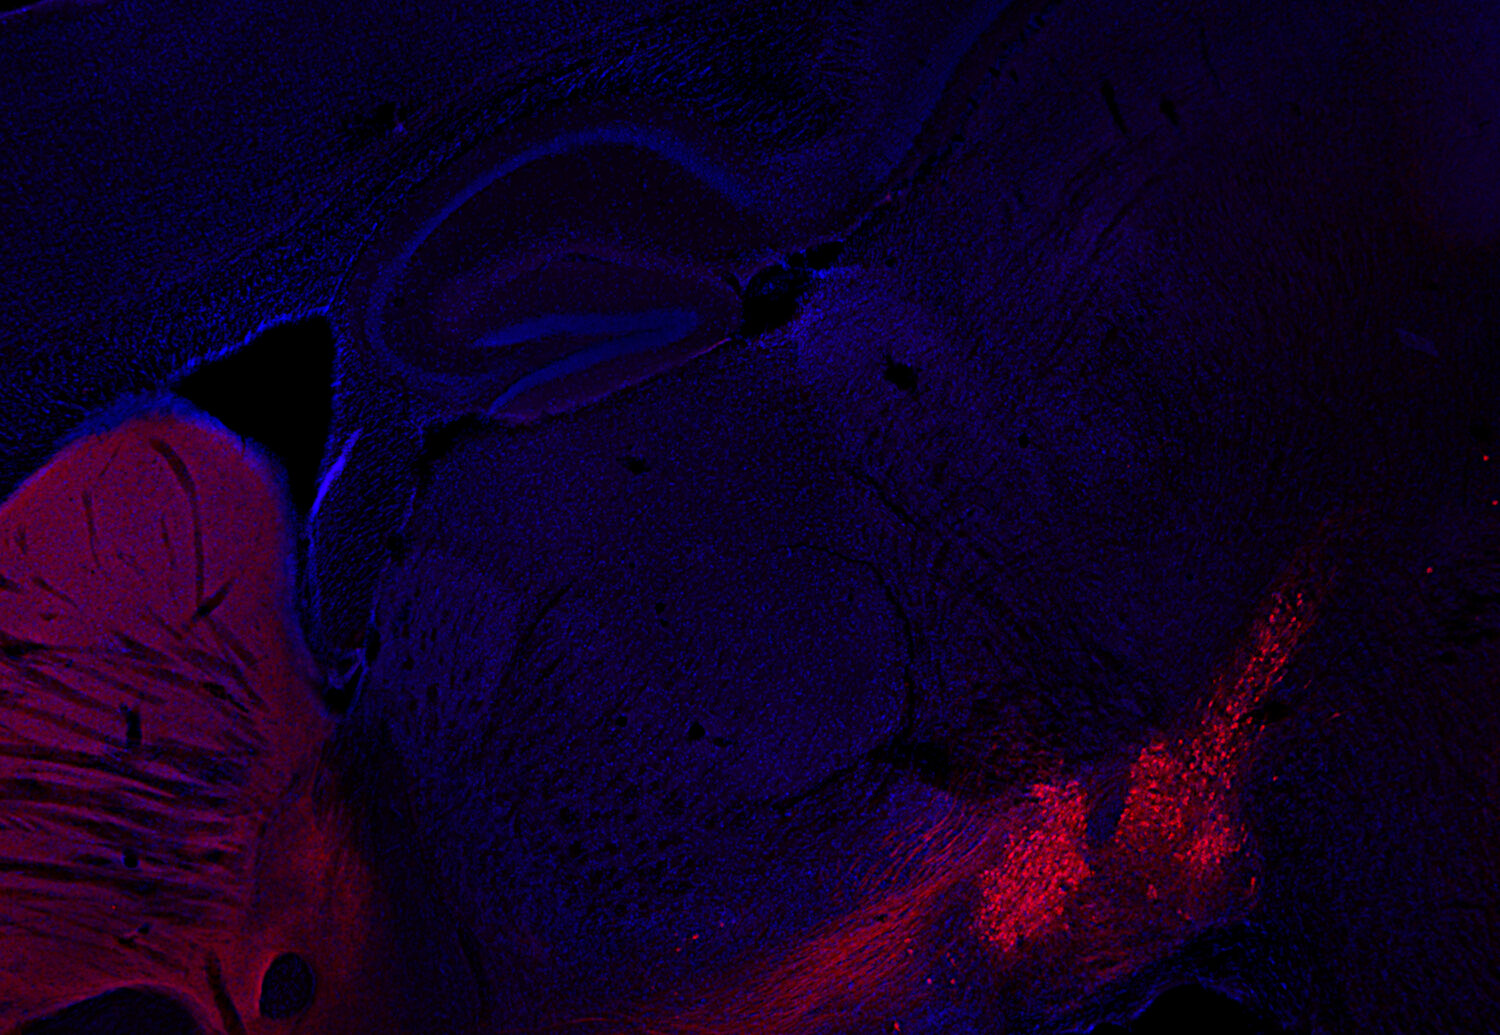

IHC: 1 : 1000 up to 1 : 10000 (see remarks) gallery

Immunohistochemistry (IHC) on 4% PFA perfusion fixed tissue with 24h PFA post fixation. Immunoreactivity is usually revealed by fluorescence or a chromogenic substrate. Some antibodies require special fixation methods or antigen retrieval steps. For details, please refer to the ”Remarks” section.

Cell reports (2023) 423: 112231. 213 211 IHC; tested species: mouse

Tyrosine hydroxylase is one of the key enzymes in the synthesis pathway of catecholamines like adrenalin, noradrenalin and dopamin and is frequently used as a marker for dopaminergic neurons. This neuronal subpopulation is especially affected in Parkinson's disease.